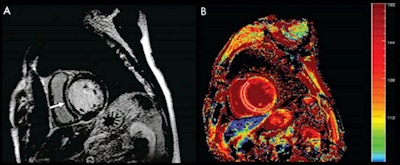

As a result of their review, the research team suggested that three particular MRI techniques show particular promise for "accurately [diagnosing] and [prognosticating] cardiometabolic risk":

- T1 mapping, which allows for assessment of the heart's vasculature, function, and myocardial tissue composition

- Cardiac MRI spectroscopy, which can quantify intramyocardial triglyceride content

- Cardiac MRI strain, which measures cardiac muscle motion and deformation